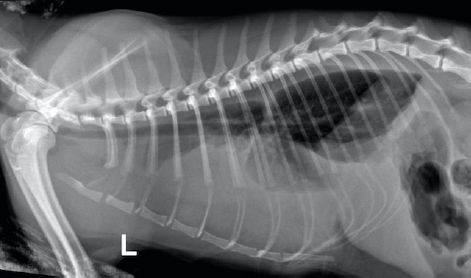

An 11-month-old British short-haired cat presented for a sudden onset of dyspnea, lethargy, and hyporexia to the emergency service of the Veterinary Medical Center of the City University of Hong Kong. The cat had been spayed 2 weeks before presentation, and shortly after suture removal, the owner had observed lethargy, hyporexia, and increased respiratory effort. Upon physical examination on day 1, there was tachypnea with a respiratory rate of 80 bpm (RR; 20–30), the heart rate was 190 (RR; 150–200), and pyrexia of 39.5°C (37.7–39.1°C). A hemogram (Table 1) showed neutropenia, lymphocytosis, and monocytosis that after correction on the cytological examination was revealed to be left shift neutrophilia instead. Additionally, there was marginal hyponatremia 148 mmol/l (RR; 150–165). Feline immunodeficiency virus and feline leukemia virus were both negative on an ELISA test (SNAP 4Dx Plus, IDEXX Laboratories, Westbrook, ME). Oxygen saturation was consistent with severe hypoxemia (<90%). Radiographs of the thoracic portion revealed pleural effusion that obscured the cardiac silhouette (Fig. 1). A cardiogenic cause of the effusion was ruled out by echocardiography.

Fig. 1. Day 1: left lateral view of thorax showing pleural effusion.